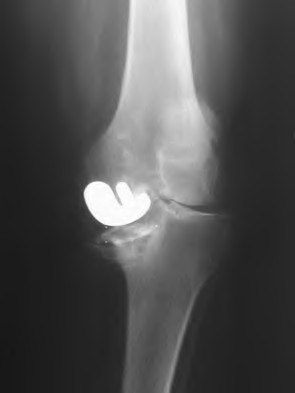

Question 37

A 35-year-old male presents with right hip pain. MRI confirms avascular necrosis (AVN) of the femoral head. Radiographs show a distinct sclerotic band and cystic changes in the femoral head, but no subchondral collapse or crescent sign. According to the Ficat and Arlet classification, what stage is this, and is core decompression generally indicated?